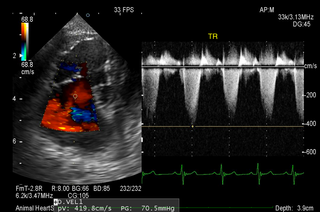

循環器内科 循環器内科 僧帽弁閉鎖不全症、肺高血圧症などを中心に扱います。 リファーラルカテゴリー 猫の腎移植プログラム画像診断科 CT/MRI/超音波検査リハビリテーション整形外科軟部外科神経科(脳脊髄・神経外科)内科鍼治療放射線治療